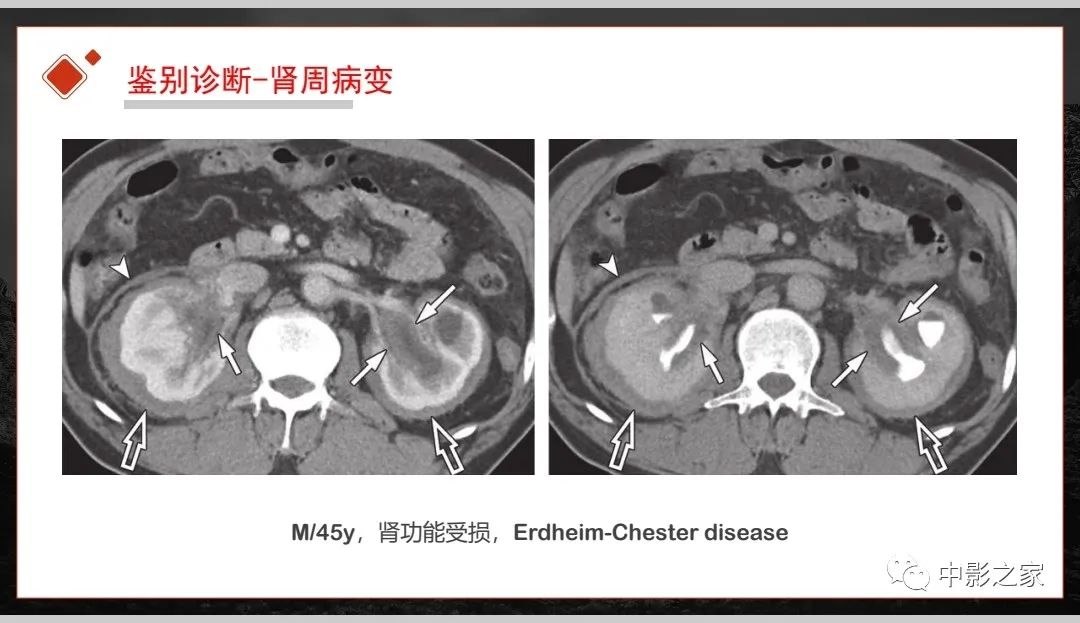

肾脏IgG4-RD临床、病理及影像特征